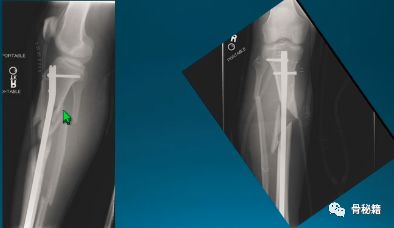

轻微粉碎的病例,多发伤患者,皮肤条件不好,不敢切开,先植入两枚阻挡钉,后方一个,侧方一个,进针之后,发现导针穿出后方……

说明这后方的阻挡钉没设计好,然后又在下方植入了一个阻挡克氏针

一个多阶段的胫骨骨折,看着移位不大

植入髓内钉后……

这样的骨折肯定长不上了,病人看了估计都会天天找你吧?翻修,近端加阻挡钉,小钢板